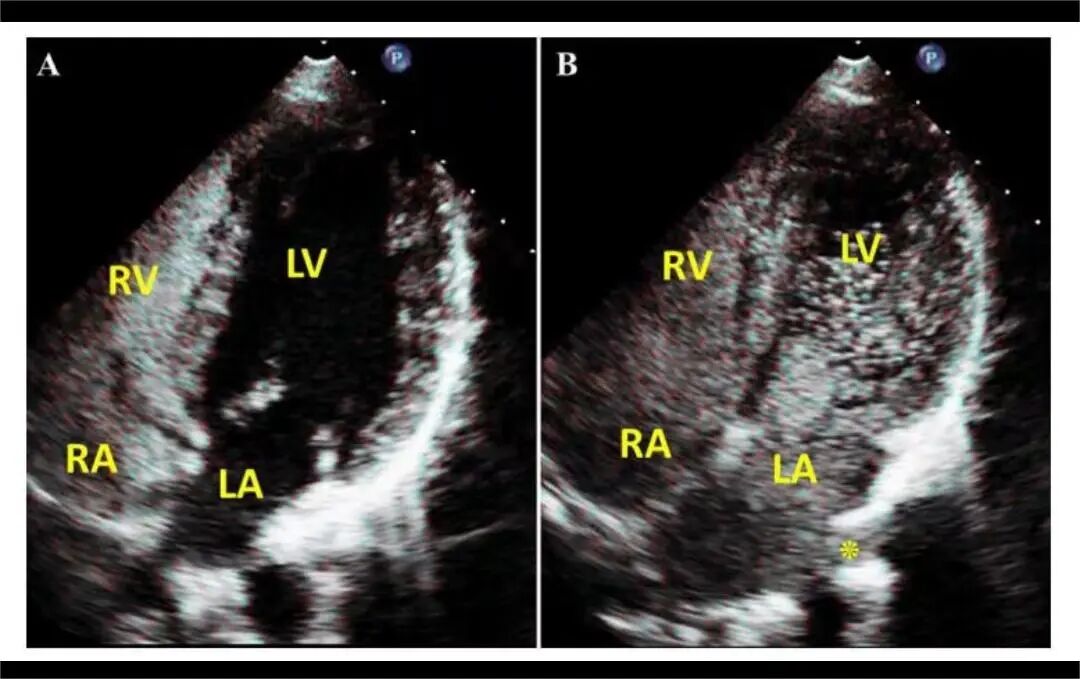

您是否也遇到过这些尴尬时刻?提重物时突然漏尿、运动时总觉下腹坠胀、更年期后总想跑厕所......这些信号可能在提醒:盆底肌需要关爱了。 盆底肌群如同"弹簧床",承托着膀胱、子宫等器官。妊娠分娩、雌激素变化、长期腹压增加等因素,都可能导致这张"网"松弛。若不及时干预,可能发展为: ▷ 盆腔器官脱垂(子宫/阴道膨出) ▷ 压力性尿失禁(咳嗽/大笑漏尿) ▷ 排便障碍(便秘/失禁) ▷ 性生活质量下降 【哪些人需要关注盆底筛查?】 ✓ 产后42天妈妈(尤其经阴道分娩) ✓ 频繁漏尿或排尿困难 ✓ 长期便秘/慢性咳嗽 ✓ 更年期女性 ✓ 性生活疼痛或下腹坠胀人群 【无创筛查新选择:盆底超声】 不同于传统指检,这项技术通过会阴体表扫描: ⏩ 多维度观察静息/收缩/用力状态 ⏩ 精准评估肌群损伤程度 ⏩ 动态捕捉器官位移情况 女性盆底三维多层显像 【检查须知】 ✔️ 避开经期 ✔️ 检查前排空膀胱 ✔️ 穿宽松裤装更方便 ✔️ 配合医生指令做缩肛/屏气动作 盆底超声检查 女性健康管理不该止于体检常规项。建议存在相关症状的女性,及时到正规医院妇产科或超声科咨询。早筛查、早干预,让盆底肌恢复应有的"托举力"。 注:部分图片来源于网络,如有侵权,请联系删除。 贵州航天医院超声科专家团队 吴艳辉 中共党员,超声科学科带头人、主任,主任医师 专业擅长:从事超声诊断工作约30年,对心血管、小器官超声、超声引导下介入等具有丰富的临床经验。 胡大海 超声科副主任,副主任医师 专业擅长:从事超声工作17年,对心血管、外周血管、浅表器官超声诊断等具有丰富的临床经验。 骆科美 中共党员,超声科副主任医师 专业擅长:从事超声诊断工作33年,对胎儿心脏及颅脑、妇产超声诊断、盆底超声等诊断具有丰富的临床经验。 刘 敏 超声科副主任医师 专业擅长:从事超声诊断工作20余年,对妇产科超声、心脏血管超声诊断具有丰富的临床经验。 贵州航天医院超声科简介 基本情况 贵州航天医院超声科配备多种超声检查设备(飞利浦彩超(IU-22、IU-Elite、HD11、Q5、Q7),迈瑞超声I9、DC-6、DC-8、GE-E8及床旁机,彩色超声诊断仪等),设有心血管诊室、妇产科诊室、腹部诊室、绿色通道、浅表小器官等检查室。 诊疗范围 科室业务覆盖腹部、泌尿、妇科、产科(常规、NT筛查、III级筛查超声检查及高危妊娠监护)、成人心脏、外周血管、浅表器官(包含甲状腺、乳腺、阴囊、眼睛等)、颅脑(小儿颅脑、成人颅脑)、小儿肺超、造影、盆底、腹直肌、肌骨神经等检查及各种介入引导。 专科特色 四肢血管超声检查、双胎产前筛查及超声监护、超声造影检查技术、介入超声临床应用、经颅脑实质超声辅助筛查诊断帕金森病、女性性早熟超声诊断、盆底超声检查等。 NT超声检查 超声介入引导 肝脏超声造影 甲状腺造影 颅脑超声帕金森辅助检查 乳腺超声造影 上肢动静脉造瘘超声检查 双胎超声筛查 下肢血管超声检查 右心造影 END